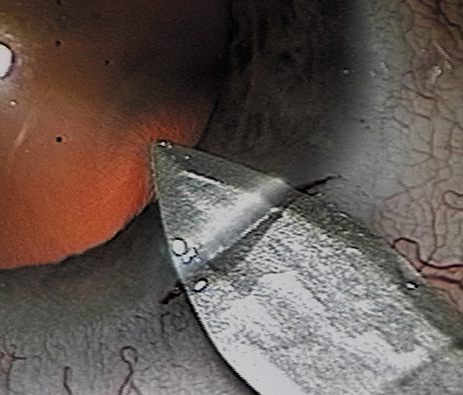

A mature cataract precludes visualization of the fundus. A B-scan ultrasonographic examination provides a real-time, two-dimensional (2D), cross-sectional image of the globe along the marked axis of the probe (Fig. 3). Cataracts are more common in patients with chronic retinal detachment, prior trauma, or intraocular tumors; therefore, a B-scan study is helpful in excluding structural posterior segment pathology before surgery on a mature cataract. Although a negative result to B-scan evaluation is reassuring, the surgeon should remember that it does not predict postoperative visual outcome. The B-scan can be thought of as a picture of Cincinnati from an airplane; the office buildings may all be standing, but you cannot tell whether the people in them are working.